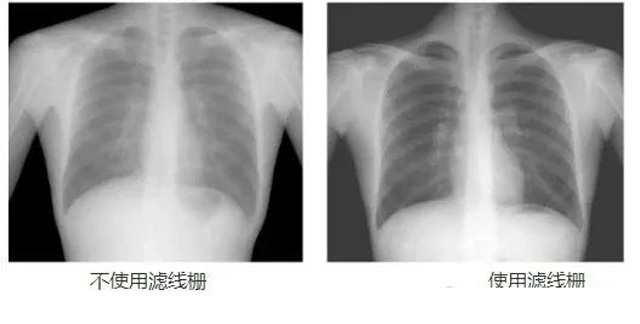

DR影像X射线在医学检查成像有着广泛的使用。但是它的散射线影响成像质量问题。滤线栅的发明使用很好的解决了这个问题,构造简单铅条粗,密度和栅比规格单一,能减散射线但吸收较多原发射线。伴随这医疗影像设备技术的发展,这个滤线栅的工艺制造技术有改进,铅条变薄,栅密度和栅比有更多的选择。特别是材料方面有新组合,填充物也依不同成像要求优化。特别是移动DR这类型的DR设备的出现,滤线栅也设计成立方便拆卸形的,方便使用。被照体情况决定是否使用,更好平衡成像质量与射线剂量。

是否使用滤线栅需综合多方面因素。当被照体厚度超15cm、千伏大于60KV等符合特定条件时,使用滤线栅可有效滤除散射线、提高影像对比度,但会吸收部分原发射线需调整曝光条件。而对于四肢等散射线少的薄部位,通常不需要使用滤线栅。总之,要根据具体的成像部位、千伏条件等实际情况来合理决定是否使用滤线栅。